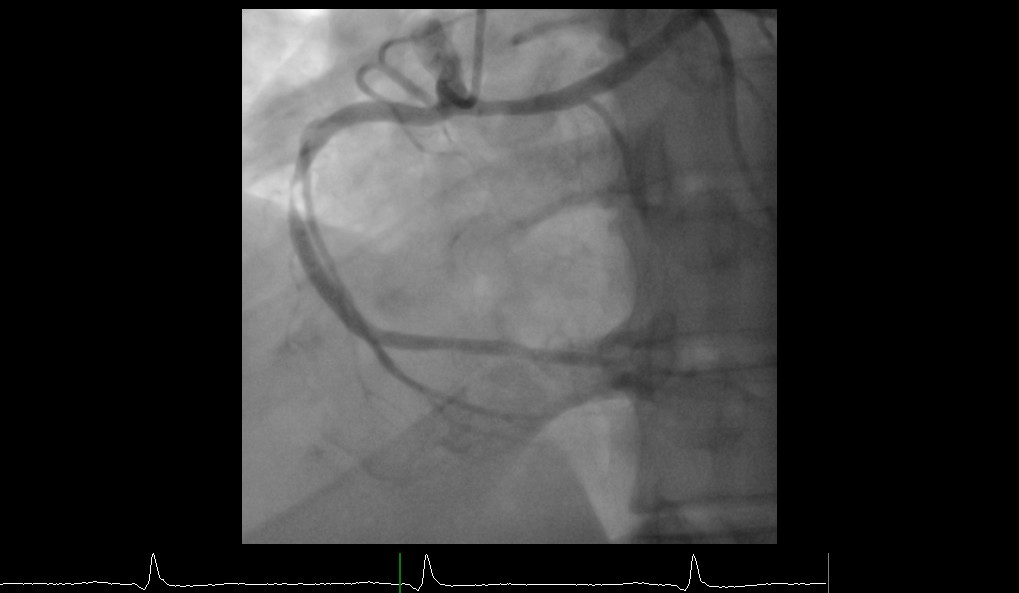

Coronary angiography was performed through right radial approach using 5F TIG catheter. Left coronary sinus contrast injection failed to show any coronary artery origin despite multiple attempts. Right coronary sinus injection showed a coronary artery arising from right coronary cusp as a single trunk which divides into RCA and left system. Left system further divides into LAD and LCX. Mid RCA showed a very tight concentric severe stenosis. Left system was devoid of any significant disease.

Percutaneous Coronary Intervention (PCI) of mid RCA: Common coronary trunk ostium was engaged with a 6F JR4.0 guiding catheter with meticulous care to prevent any ostial injury. Mid RCA lesion crossed with a 0.014¡± BMW wire. Predilated the lesion with 2.5x12mm semi compliant balloon. Stenting of the lesion was done using a DES (3.5x23mm) with final good result. A cardiac CT was done following PCI which confirmed the angiographic findings and found normal subpulmonic non-malignant course of left branch vessel (Lipton's class R II A).